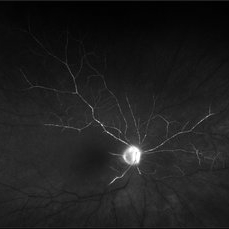

Wyburn Mason Racemose Angiomatosis

Color fundus montage of an 13-year-old female with arteriovenous malformation (Wyburn Mason Racemose Angiomatosis) affecting her right eye. The retinal arteriovenous malformation appears to be stable. She presented with NLP in the eye, strabismus, and peripheral retinal ischemia. She is at risk for neovascular complications; however, she is currently being treated with Sirolimus. Since she is on this systemically, there is no need to perform intraocular anti-VEGF injections or PRP laser. She also presented with optic atrophy affecting her left eye, secondary to chiasmal involvement of arteriovenous malformation. She has had a potential progressive visual field loss involving the temporal aspect of her visual field from the left eye. There is sector optic atrophy. Presumably, this is due to a compressive effect of her arteriovenous malformation on the nasal nerve fiber layer (corresponding to the temporal visual field) crossing to the right occipital cortex at the chiasm.

Photographer: Olivia Rainey

Imaging device: Topcon 50dx

Condition/keywords: arteriovenous malformation, color fundus photograph, color photo, montage, peripheral ischemia, Sirolimus